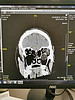

Пациенту было срочно выполнено КТ-исследование, которое показало, что зрительный нерв не поврежден. С момента получения травмы к тому времени прошло около 5 часов. Пациент был проконсультирован офтальмологами, и для того, чтобы избежать удаления глаза, было принято решение экстренно оперировать. Операция была проведена в два этапа совместными усилиями хирургов челюстно-лицевого и отоларингологического отделений.